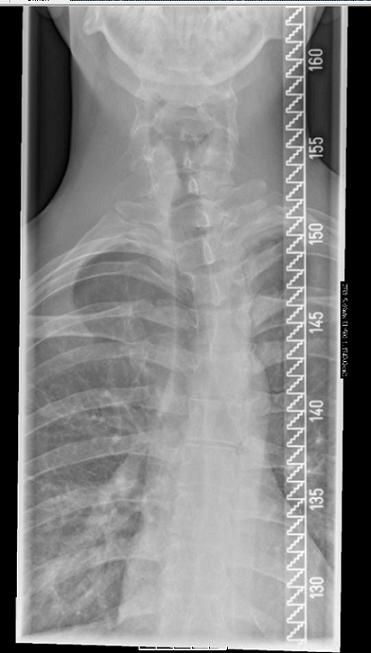

- Brustwirbelsäule

- BWS stehend.jpg (28.43 KiB) 2505 mal betrachtet

Zuerst mal zu dem RöBi. Für mich sieht es so aus, als ob schon das Becken schief steht und die WS nicht gerade steht. Eigentlich sind im unteren Bereich nur mehrere sehr kleine, sich z.T. gegenseitig aufhebende Krümmungen zu erkennen. Durch den Schiefstand in der Beckenregion kommt die WS bis zur oberen BWS aus dem Lot, was durch eine mäßige (Gegen-) Krümmung von ca. 19° nur unvollständig ausgeglichen wird. Die Krümmung der oberen BWS wird wiederum durch eine Krümmung im BWS-HWS-Übergang kompensiert.